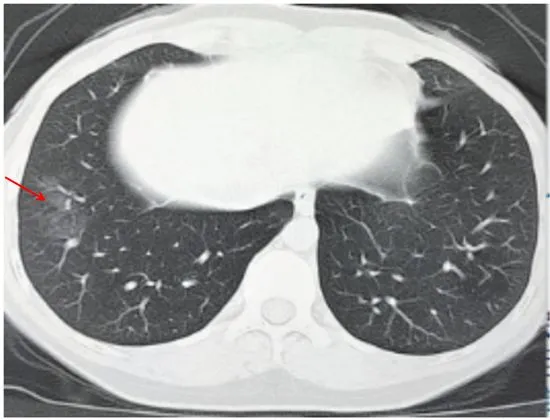

(六)长轴与胸膜平行

病灶沿着胸膜下呈长条片状分布,一般不引起胸膜反应

提示病理改变:病变首先累及皮层肺组织,不按肺段解剖分布,对细菌性肺炎病灶分布有一定的鉴别意义(图 2-6)